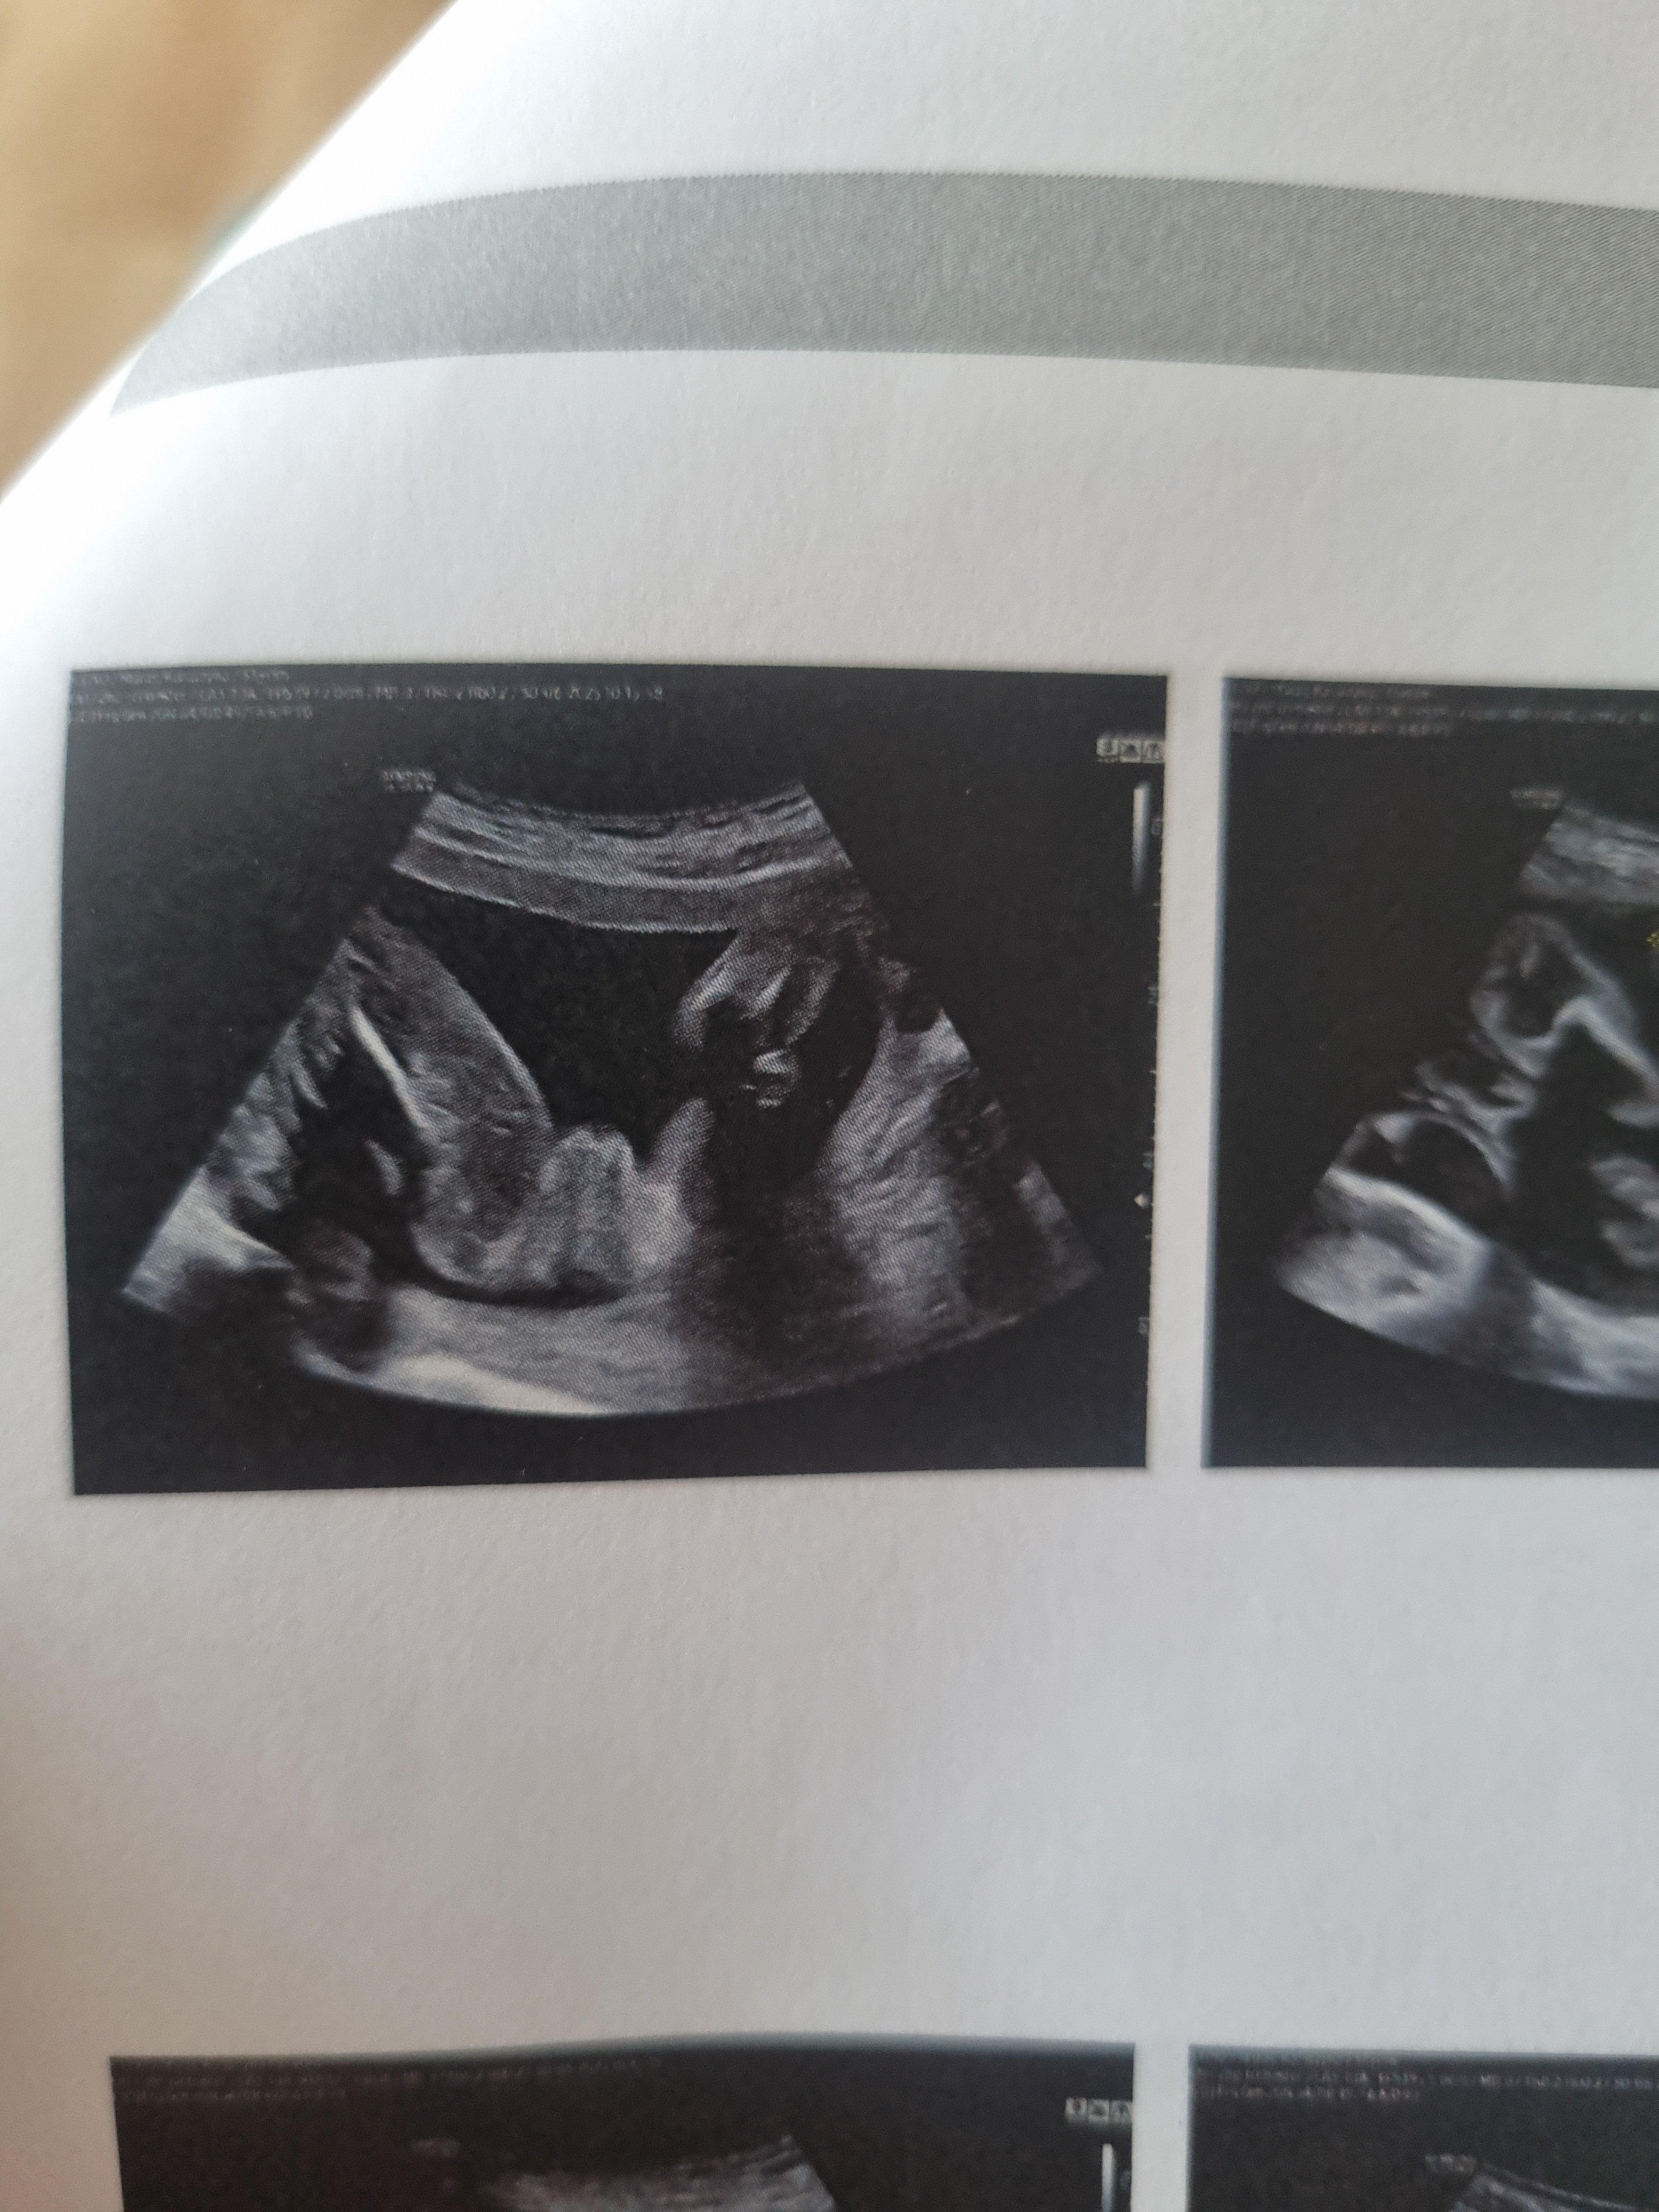

Według mnie takW 13 jeden lekarz ze dziewczynka a drugi w 17 ze chłopczyk ale czy na pewno

Jak dla mnie wyraźnie widać mosznę i siusiaczkaW 13 jeden lekarz ze dziewczynka a drugi w 17 ze chłopczyk ale czy na pewno

Wygląda na dziewczynkę.Jaka to może być płeć 22tc?

A po czym to można stwierdzić?po jakich detalach?Wygląda na dziewczynkę.

jeśli jest to zdjęcie zrobione tak jakby od dołu to po bokach masz uda a na środku są wargi sromowe. Jeśli bylby to chłopiec to widać by było jądra i penisa.A po czym to można stwierdzić?po jakich detalach?